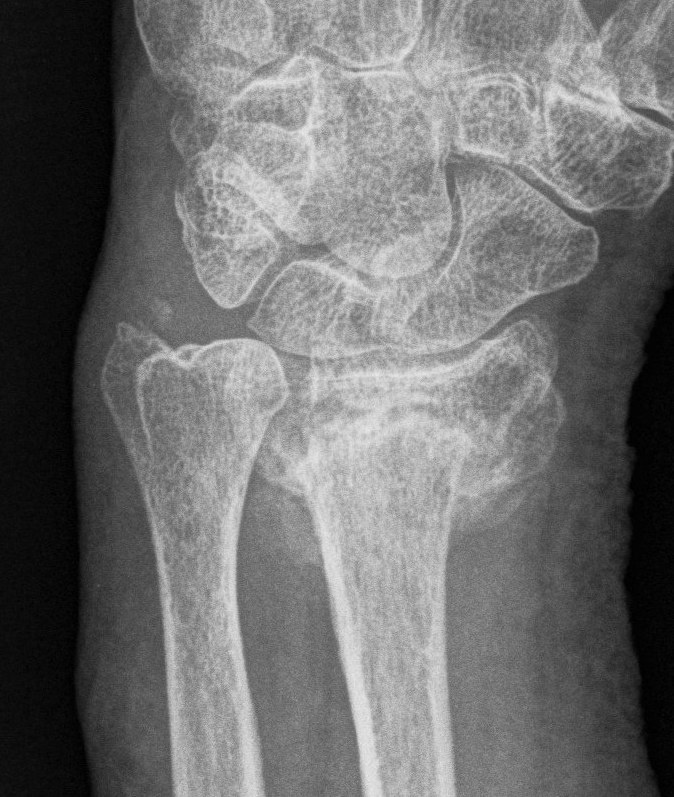

Xray

Bilateral xrays

PA film in neutral

- wrist neutral

- elbow & shoulder at 90°

Malunion

| Radial shortening | Radial inclination | Positive ulna variance |

| Dorsal tilt > 15 degrees | Volar tilt > 10 degrees | Articular step > 3 mm |